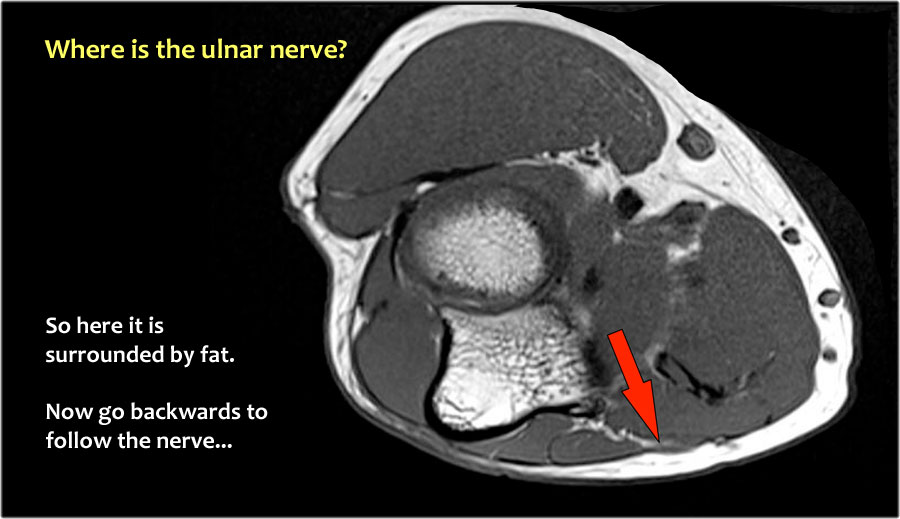

Một cách để thực hiện là đi theo các cấu trúc về phía xa cho đến khi tìm thấy dây thần kinh trụ ở phía xa tại vị trí bình thường của nó ở vùng cẳng tay gần được bao quanh bởi mô mỡ.

Sau đó khi bạn theo dõi nó về phía gần, bạn sẽ nhận thấy rằng đây là một trường hợp chuyển vị dưới da.